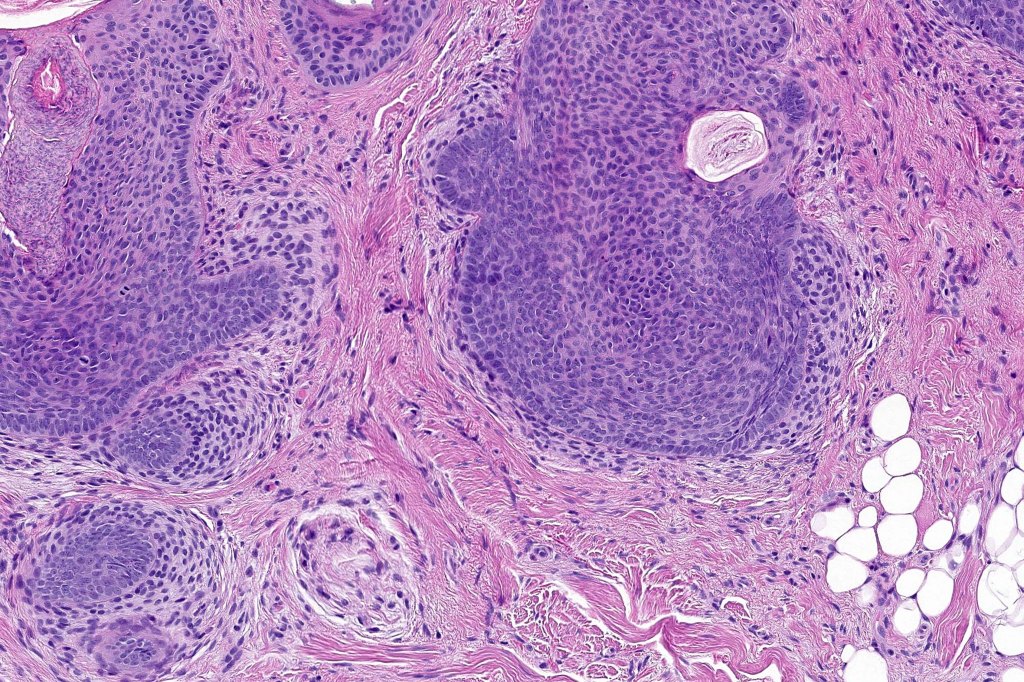

Histological features

•Biphasic tumors comprising germinative epithelial and mesenchymal components

•Sharply circumscribed nodule, sometimes with a pseudocapsule

•Uniform basaloid cells with peripheral palisading and often marked mitotic activity

•Variable keratin cysts

•Sebaceous & glandular differentiation

•Stromal component associated with indentation of epithelial component- follicular mesenchymal bodies (uncommon, more often seen in trichoepithelioma)

•Stromal amyloid often present

•Trichogerminoma (see images)